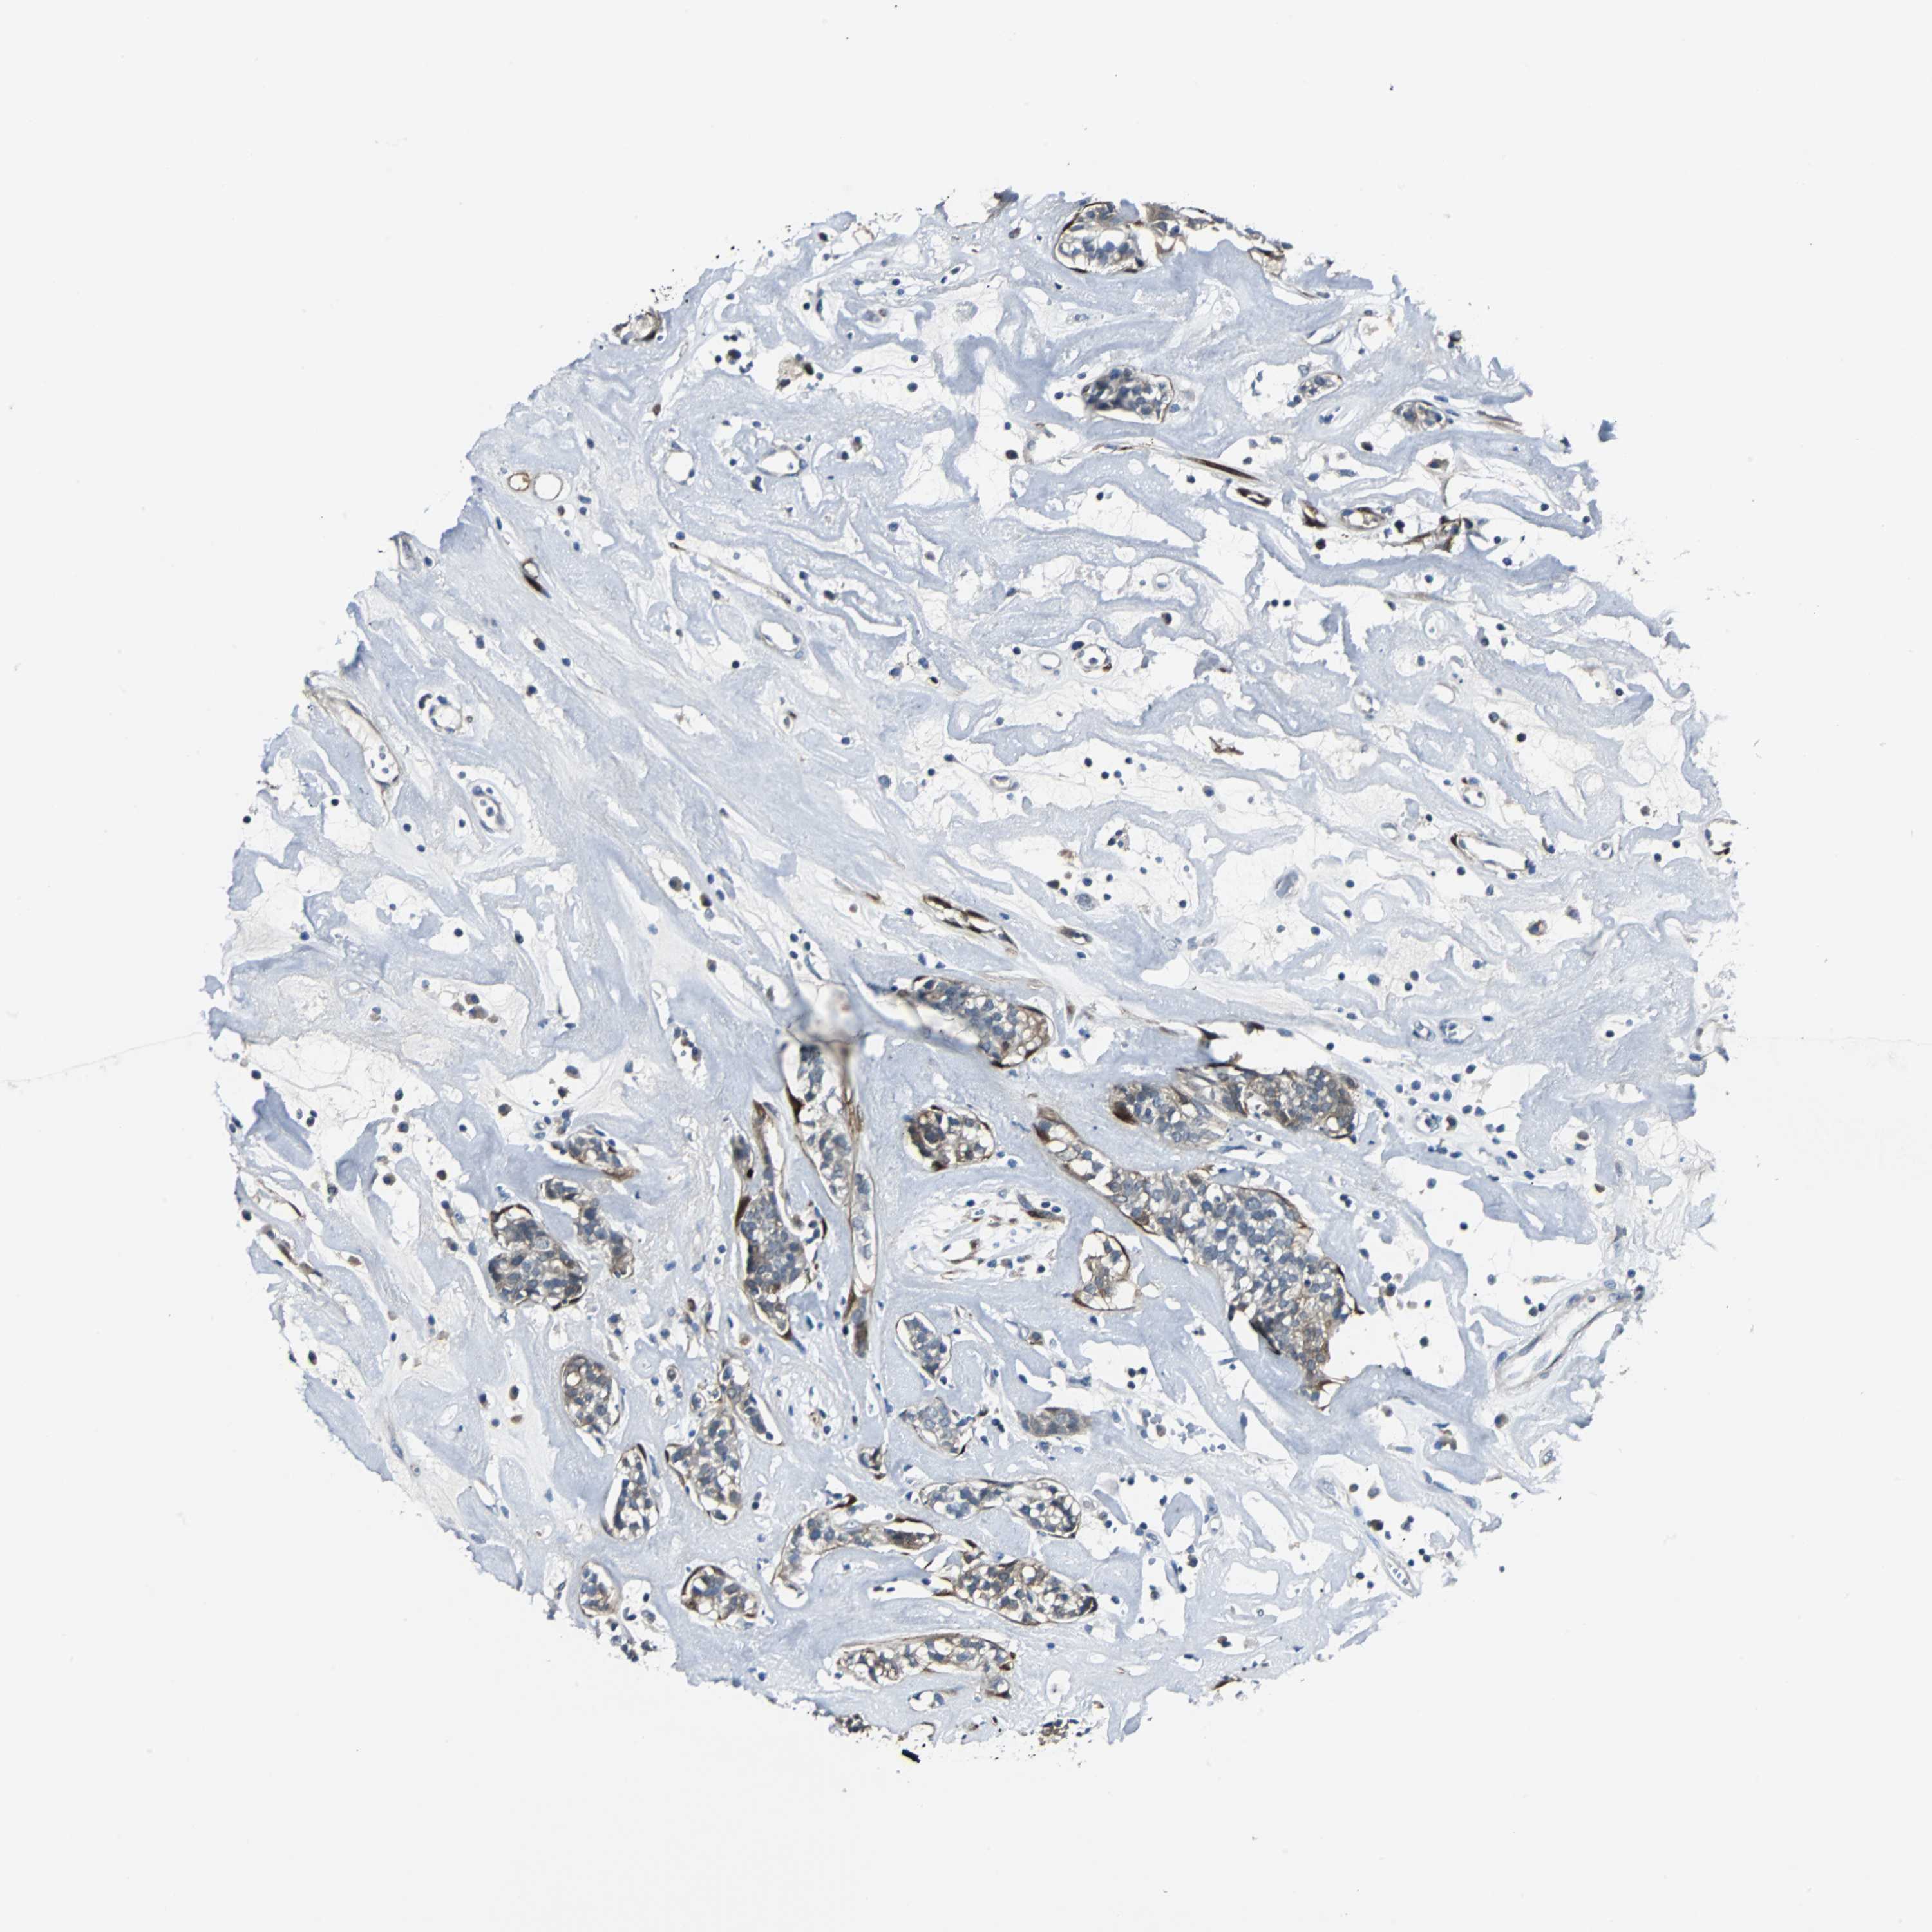

HEAD AND NECK CANCER - Protein expressioni

A mouse-over function shows sample information and annotation data. Click on an image to view it in a full screen mode. Samples can be filtered based on level of antibody staining by selecting one or several of the following categories: high, medium, low and not detected. The assay and annotation is described here.

Antibody stainingi

Antibody staining in the annotated cell types in the current human tissue is reported as not detected, low, medium, or high, based on conventional immunohistochemistry profiling in selected tissues. This score is based on the combination of the staining intensity and fraction of stained cells.

Each image is clickable and will lead to virtual microscopy that enables deeper exploration of all samples and also displays staining intensity scores, fraction scores and subcellular localization as well as patient and tissue information for each sample.

Antibody HPA005922

Antibody HPA006028

Antibody CAB008368

Staining

High

Medium

Low

Not detected

Intensity

Strong

Moderate

Weak

Negative

Quantity

>75%

75%-25%

<25%

None

Location

Nuclear

Cytoplasmic/membranous

Cytoplasmic/membranous,nuclear

Neoplasm, malignant, NOS

Carcinoma, NOS

Adenocarcinoma, NOS

Squamous cell carcinoma, NOS

Squamous cell carcinoma, metastatic, NOS

Adenoma, NOS